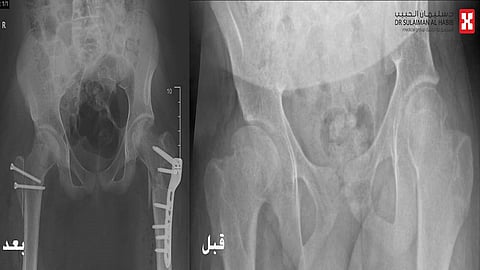

مفيداً بأنه تم إخضاعه لفحوصات بالرنين المغناطيسي (M.R.I) والتصوير المقطعي (C.T Scan) والأشعة السينية الرقمية (Digital X-rays) ، والتي حددت بدقة عالية وجود ميلان حاد بالحوض وقصور في حركة مفصل الوركين واختلاف طول الفخذين، موضحاً أن الفريق الطبي عقب دراسته للحالة قرر التدخل الجراحي، وذلك للحيلولة دون إصابته بمزيد من الميلان في عظم الحوض وخطورة الاصابة بخشونة مبكره وجنف العمود الفقري الثانوي.

وأوضح الدكتور الرفاعي أن العملية استغرقت 5 ساعات متواصلة تحت التخدير العام، وتم فيها عمل خلع جراحي لمفصل الورك بعملية معقدة تعرف بأسم ( procedure Modified DUNN)، تبع ذلك إجراء عزل للشرايين المغذية لرأس عنق الفخذ الأيسر وتطويل رقبة الفخذ النسبي، بالإضافة إلى ترميم كامل مفصل الوركين وإعادة استقامة عظم الحوض.